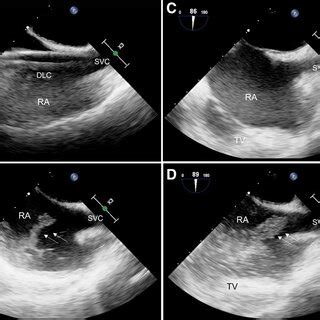

So, why is this bicaval view so crucial? Think of the heart as a bustling city, and the vena cava are the highways bringing in all the traffic (blood) from the rest of the body. The bicaval view gives us a panoramic view of these highways as they enter the heart’s main station (the right atrium). This view is your go-to for checking the size and shape of these major vessels and how they function. This is especially vital when checking for clots, which can be deadly. It also helps in assessing the pressure within the right atrium, a key indicator of heart health. Furthermore, it gives a good look at the tricuspid valve, ensuring it’s working properly. This view is also super helpful in assessing patients with shortness of breath, chest pain or other symptoms related to heart problems, the bicaval view can provide crucial insights.

Now, let’s get into the nitty-gritty of how to get the perfect view. First, remember the patient should be lying on their left side, which is known as the left lateral decubitus position. This helps bring the heart closer to the chest wall. The probe itself is the magic wand, and the specific type you use (usually a phased array) is designed for this kind of imaging. Then comes the tricky part: the probe position. Imagine you are trying to catch the sun at the optimal angle. The goal is to position the probe under the sternum (the breastbone), aiming slightly towards the patient’s right shoulder. The idea is to align the ultrasound beam with the vena cava so you can see them clearly as they enter the right atrium. Be patient and adjust slightly until you get the best image. The orientation marker on the probe is your best friend here; it should point toward the patient’s right. It may take some practice, but you’ll get the hang of it.

Alright, let’s break down the process step-by-step for the bicaval view echo probe position . First, you’ll need the right equipment: an ultrasound machine, the right kind of probe (usually a phased array), and some acoustic gel (that stuff that makes everything glide smoothly). The patient should be positioned in the left lateral decubitus position. This positioning moves the heart closer to the chest wall, making it easier to get clear images. Now, apply the acoustic gel liberally to the probe head. This helps eliminate air pockets and ensures good contact with the skin. Place the probe just below the sternum, aiming towards the patient’s right shoulder. Gently angle the probe and try to visualize the right atrium and the vena cava. Remember to keep the probe flat against the chest wall to get the best contact and minimize any loss of image quality. Slight adjustments are often necessary to find the sweet spot, the one where the images are super clear. Scan through the various angles to see which one gives you the best picture of the superior and inferior vena cava entering the right atrium.

Even with practice, you might run into a few snags when trying to find the perfect bicaval view echo probe position . One of the most common issues is poor image quality . This can be due to a variety of factors: the patient’s body habitus (body type), air pockets between the probe and skin, or incorrect probe angulation. If you’re struggling to get a good image, try adjusting the probe’s angle, and ensuring that there are no air bubbles, and make sure that the probe is making good contact with the chest wall, then adjust the machine settings to optimize the image. In some cases, patients with a larger chest size may require more adjustments. Another challenge is identifying the structures correctly. The superior vena cava can sometimes be mistaken for the ascending aorta. Make sure to carefully trace the vessels back to their origin. Use color flow Doppler to help differentiate between the two; the superior vena cava will show venous flow (away from the probe). Also, make sure you’re looking at the right anatomical area. A good starting point is the subcostal view, and then you can gradually move the probe up to the parasternal. Sometimes it helps to take a deep breath in and hold it. This maneuver can bring the heart closer to the probe and make imaging easier. Remember, every patient is different, and being adaptable is key.